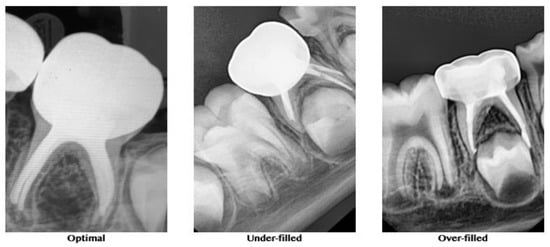

2.3.2. Quality of Obturation

A postobturation radiograph was taken for further evaluation and comparison of the quality of obturation between the groups. The quality of the root canal obturation was recorded, according to O’Riordan and Coll [23] as optimal (1 mm short of the apex), underfilled (2 mm short of the apex), or overfilled (beyond the apex) (Figure 3).

Figure 3. Representative radiographs for the quality of obturation.

3.2. Quality of Obturation

In the XP-endo Shaper group, 19 of the 25 teeth were optimally filled, 2 were underfilled, and 4 were overfilled. In the Kedo-S group, 15 of the 25 teeth were optimally filled, 3 were underfilled, and 7 were overfilled. Finally, in the hand K-file group, 12 of the 25 teeth, were optimally filled, 8 were underfilled, and 5 were overfilled. The results of the quality of obturation are presented in Table 3. The teeth treated with the XP-endo Shaper exhibited significantly better obturation results compared to the other groups (p < 0.01, Chi-square test).

Evaluating the quality of obturation in the present study was limited to the method proposed by O’Riordan and Coll [22] and used the criteria of optimal (1 mm short of the apex), underfilled (2 mm short of the apex), or overfilled (beyond the apex). Obturation in the current study was carried out using Metapex, an iodoform-based calcium hydroxide cement. This cement possesses better resorbing ability and disinfectant properties compared to conventional zinc oxide eugenol cement. Additionally, it is resorbed by macrophages faster than the primary root [29]. This cement is advantageous, exhibiting no foreign body reaction when extruded into furcal or apical areas when used for obturation. There are no reports of any effect of the extruded Metapex on permanent tooth buds to date. It has also been observed that the extruded cement usually resorbs within 1–2 weeks [30]. The present finding that root canals instrumented with the XP-endo Shaper allowed a more frequent (76%) optimal obturation result, according to the above criteria, may be explained by previous ex vivo studies of this adaptive file. The ability of this file to adequately instrument and clean the canals of permanent teeth with an oval cross-section has been studied using microCT [20,27,31,32]. It has been demonstrated that the XP-endo Shaper resulted in better 3D instrumentation than rotary files, affecting a higher percentage of the root canal walls [20,27,31,32]. It could be that a cleaner canal, without debris remnants in its recesses, is easier to obturate with the method used in the present study.